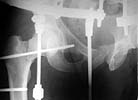

See attachment for AP and Judet views after external fixation. Our pelvic guys tried to reduce the acetabulum with the transarticular pin inserted through the lower part of the head. They are satisfied with the pattern and plan to insert a percutaneous screw to fix the position during a surgery for the neck and shaft fracures.